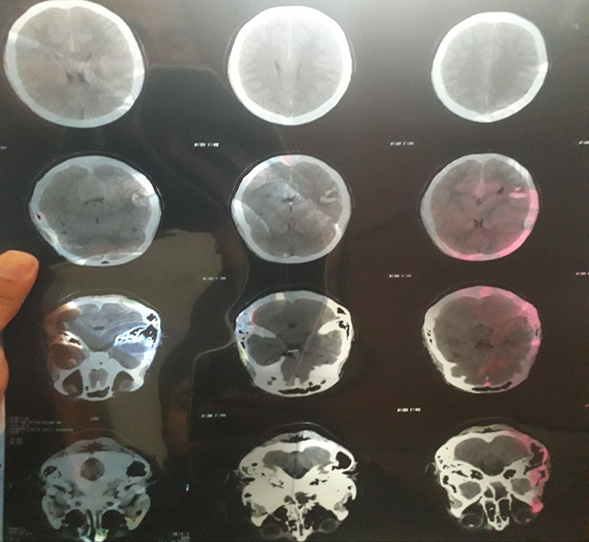

Simple cranial computed tomography (CT) documented images with intracerebral hemorrhage (Figure 1). Reason why it was decided to admit the patient to the neurology department of the hospital, as well as coordinated management with the neurosurgery department, non-surgical management was chosen at the time, the patient was kept on continuous monitoring, complete rest, intravenous solutions, pain management, as well as extravascular nutritional support. Due to clinical improvement and reduction in cerebral hemorrhage, he was discharged 2 weeks after admission to his home, and referred to the neurology.

Figure 1 Hematoma with heterogeneous density, CT, taken in the first 4 hours of the condition.

In recent years, several articles have described cases of hemorrhage in contact sports, in some of them the growth of the hematoma in the initial phase, both in brain CT. In this report, the only sign on the tomography that has shown an association with a longer hospital stay has been the irregular shape of the hematoma, which is associated with greater mortality in the first seven days, although when categorizing the GCS score below 13, between 12 and 5. The rest of the signs (heterogeneous density, liquid level and mixture sign) are not associated with higher mortality at 7, 30 and 90 days.

The heterogeneous density of a hematoma reflects bleeding at different times, suggestive of a dynamic process, where bleeding may still be active. Likewise, it may reflect multifocality. More hypodense areas are related to recent bleeding, and hyperdense areas are related to older bleeding, which represents an organized thrombus.13 This heterogeneity has been studied since the 1980s in epidural and subdural hematomas, and the swirlsign was described, which was a hypodense area encapsulated in the hyperdensity of the hematoma.17 This sign was associated with active bleeding, which was demonstrated in surgical interventions for epidural and subdural hematomas.18 In recent years, the heterogeneity of ICH has been associated with early hematoma growth, as well as various signs (mixing sign, fluid level), which could be considered part of the concept of heterogeneity.